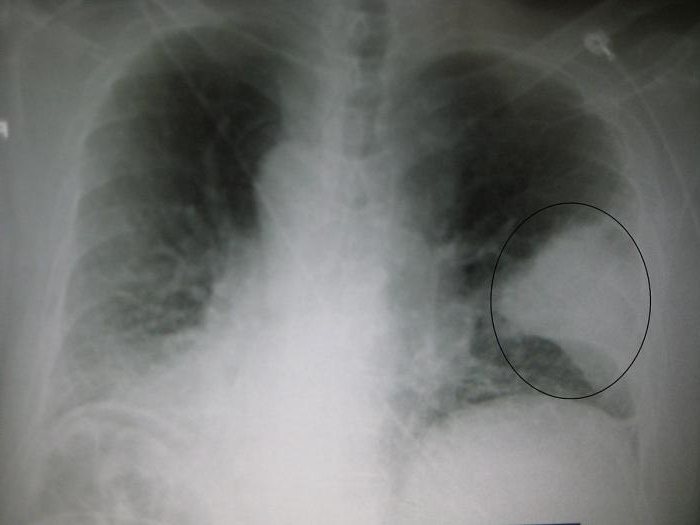

- Рентгенография грудной клетки.

- Данные дополнительных обследований. Таких, как рентген грудной клетки, биохимический анализ мокроты.

- Флюорография.